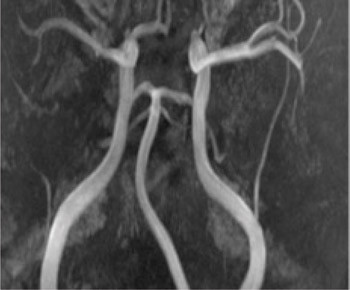

A person in his 20s with known migraine with aura developed infarcts in the right middle cerebral artery and both anterior fields of supply (Figure 1 shows a magnetic tomography diffusion weighted series). Cerebral computed and magnetic tomography with magnetic resonance angiography (MRA) after admission showed normal blood flow and no sign of dissection or vasculitis. Hemicraniectomy became necessary after development of malignant cerebral oedema. MR angiography the first postoperative day showed open arteries (Figure 2 shows an open carotid top (white arrow), normal basilar top (red arrow), and a non-closed circle of Willis, an anatomically normal variant (stars). Testing for illegal drug use, anticardiolipins, anti-nuclear antibodies, neurone antibodies and tumour markers was negative. Transoesophageal echocardiography showed a minimally patent foramen ovale, according to a cardiologic evaluation unlikely to be related to the episode. The patient developed severe brain stem involvement and MR angiography showed narrowing of the posterior branch of the basilar artery (arrows in Figure 3). Arterial vessel spasms were suspected retrospectively. The first suspected vessel spasm, in the right – middle/anterior branch, remained undocumented. The second, in the posterior branch of the basilar artery, was documented postoperatively (arrows in Figure 3). Images of several newly developed infarcts in the posterior circulation are not shown. Three weeks after the hemicraniectomy the angiogram was normalised (Figure 4).

The patient was taking one packet of loose snuff with 400 mg nicotine daily. Assuming that 30 % is absorbed, this amount of snuff corresponds to the nicotine content of 173 strong cigarettes. The risk of cerebral stroke is increased more than nine times by the combination of tobacco and migraine with aura. Vessel spasms are a suspected as a causal factor. Nicotine is a known vasoconstrictor, with provocation of vessel spasms both during use and with nicotine abstinence. We therefore suspect the high snuff intake, combined with underlying migraine with aura as the probable cause of cerebral arterial vessel spasms in the middle/anterior branch and the posterior branch of the basilar artery.